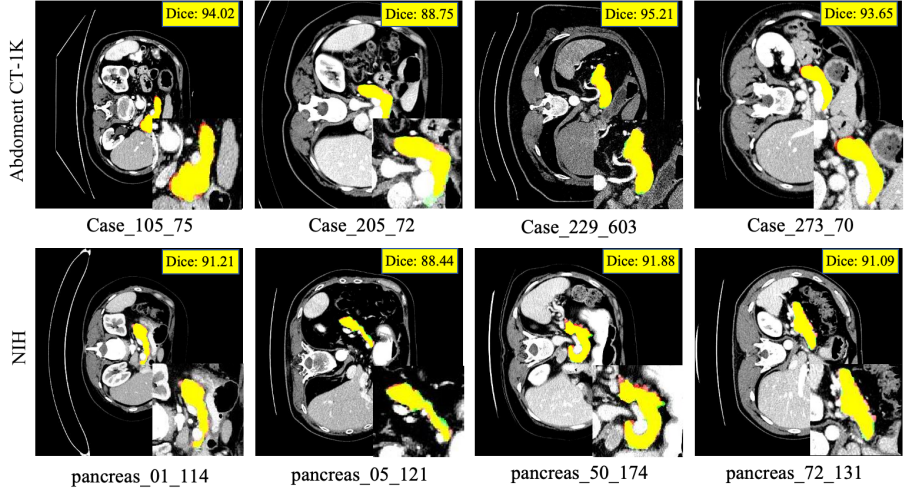

Refer to caption

Figure 2: Segmentation results on the AbdomenCT-1K dataset (first row) and the NIH dataset (second row). Contours: Red = Gold Standard, Green = Predicted Result.

Figure 3: Segmentation results on the MSD dataset (first row) and the WORD dataset (second row). Contours: Red = Gold Standard, Green = Predicted Result.

5.2.3 Multi–Dataset Robustness Evaluation

Similar results could also be obtained on other datasets, and the proposed model demonstrated accurate and robust performance. Compared with the existing state-of-the-art methods shown in TABlE 3, the mean and variance of the proposed method are very stable. The proposed model achieved the optimal results on the main evaluation metric Dice, and the optimal and suboptimal results on the Jaccard metric. While maintaining the coverage rate, the other two auxiliary indicators also demonstrated excellent performance. As shown in Fig.2 and Fig.3, most of our segmentation results overlap with the gold standard on four datasets.